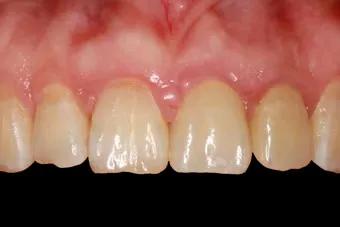

3.种植牙

与活动假牙、烤瓷牙牺牲周围牙齿保全自己的做法相比,种植牙是能和真牙打成一片的。

种植牙是将种植体(金属钛,可与人体结合)放入缺牙区的牙槽骨充当人工牙根,不依靠邻牙就能站稳脚跟。

种植牙形态美观、舒适、固位稳定,功能与天然牙近似,能高效地行使咀嚼功能,且无需磨损旁边的牙齿,对邻牙没有任何伤害。

无需活动牙类似的卡环或基托,没有异物感,寿命长,只要不是遇人不淑没种好,种上的牙齿至少能用30余年。

而且种植手术是一个较小的手术,类似拔牙手术,采用局部麻醉,手术只需要半小时左右即可完成,创伤小,术后2小时即可进食。缺点是种植牙的成本比较高、对口腔医生的技术要求也较高,治疗费用相对比较高。